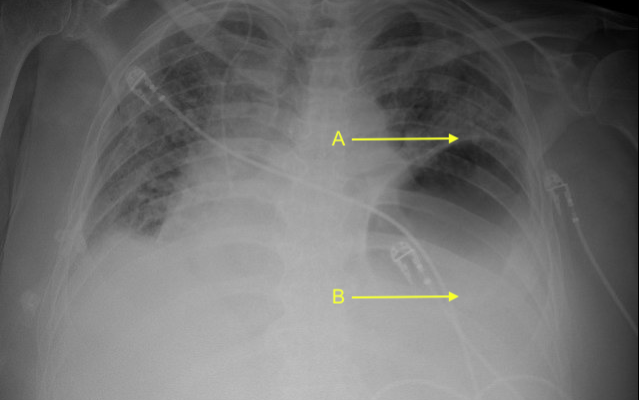

CXR first, then POCUS, then CT. Answers at end of thread

Where is the left hemidiaphragm located? and what is happening here?

(poll in next question)

Answers to above questions - CXR and POCUS labeled here

But why?

This is due to a hiatal hernia, with upper portion of the stomach passing above the diaphragm and into the thorax.